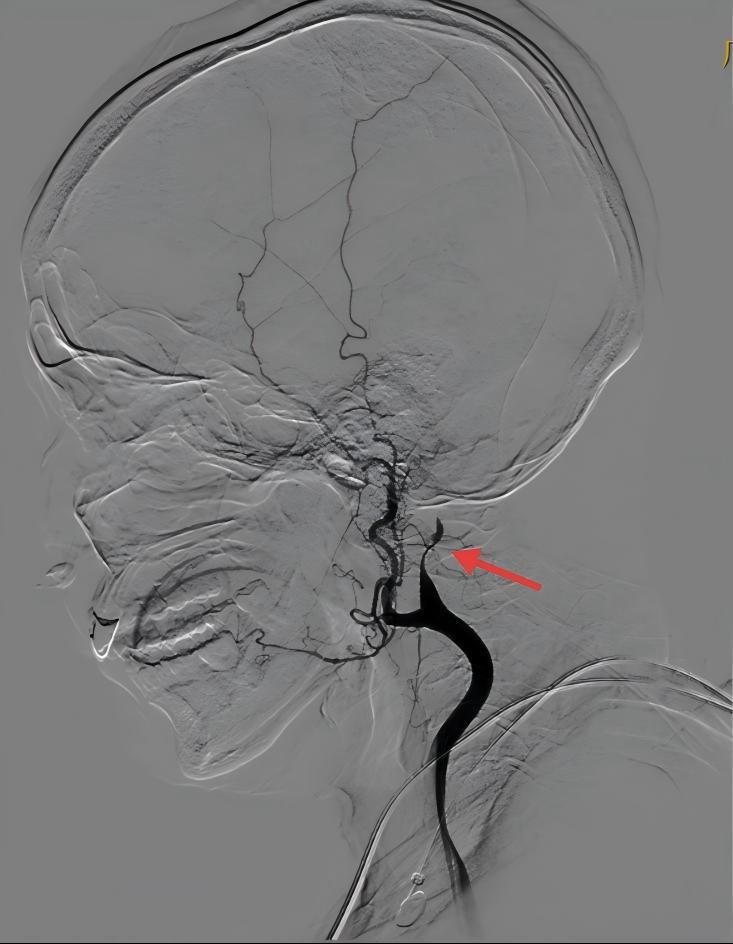

深夜的介入导管室内,陈洪乔副主任医师及其团队熟练操作,快速完成造影。造影见左侧颈内动脉栓塞,术中予支架拉栓+抽吸,抽出两块暗红色血栓,再次造影显示左侧颈内动脉完全再通。介入团队仅一次操作就成功开通闭塞的血管,从穿刺成功到完全再通仅40分钟。

左侧颈内动脉闭塞(红色箭头)